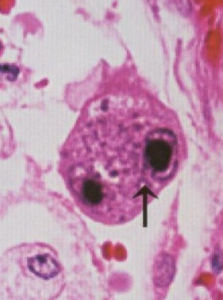

i. 血樣本(全血、單個核細胞、血清或血漿)、尿及其他體液包括肺泡灌洗液(最好取脫落細胞)和病變組織中獲得如下病毒學證據:(1)、病毒分離:是診斷活動性HCMV感染的“金標準”;(2)、電子顯微鏡下找病毒顆粒和光學顯微鏡下找巨細胞包涵體,但此法陽性率較低;(3)、免疫標記技術檢測病毒抗原:IEA、EA、pp65抗原等;(4)、逆轉錄PCR法檢測病毒特異性基因轉錄產物,陽性表明活動性感染;(5)、實時螢光定量PCR法檢測病毒特異性DNA載量。由於螢光定量方法的特異度及敏感度均較高,且操作簡便,與pp65抗原血症的準確度類似,目前在臨床套用較為廣泛[4]。HCMV-DNA載量與活動性感染呈正相關,高載量或動態監測中出現載量明顯升高提示活動性感染可能。血清或血漿樣本中HCMV-DNA陽性時為活動性感染的證據;全血或單個核細胞陽性時存在潛伏感染的可能,高載量支持活動性感染。在新生兒期檢出病毒DNA是原發感染的證據。間接證據